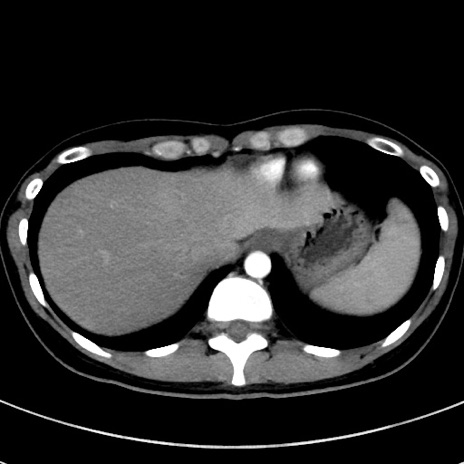

症例17(横断像)

【症例】20歳代女性

【主訴】嘔吐、下腹部痛

【現病歴】昨日夕食後に嘔吐し下腹部痛が出現。本日になっても嘔吐持続し改善しないため来院。

【身体所見】意識清明、BT 37.2℃、BP 108/67mmHg、腹部:平坦、やや硬、下腹部正中から右にかけて圧痛あり、反跳痛軽度あり、tapping pain(+)。

【データ】WBC 13600、CRP 14.94